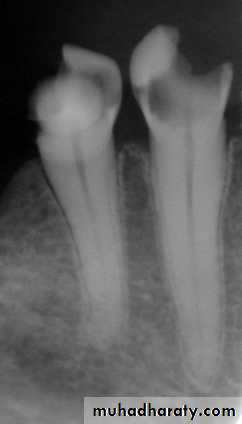

1.1 Dental pain (Pulpal , Periodontal pain , Gingival pain)